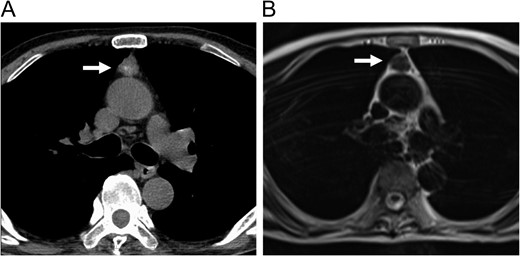

Enhanced CT (A) and MRI (B) of the chest revealed an anterior mediastinal tumor.